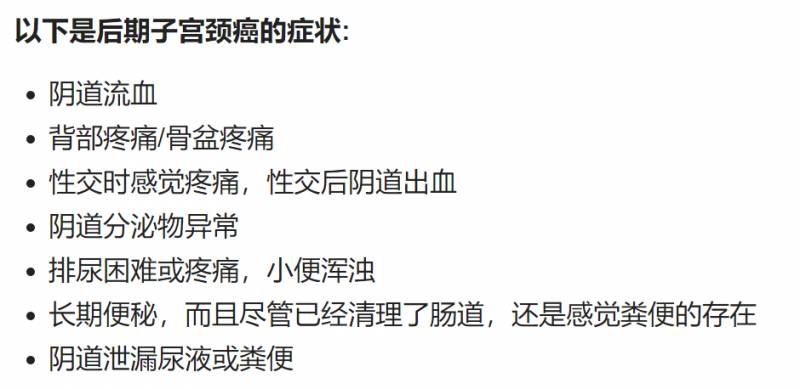

谢医生的主题围绕宫颈癌、子宫癌、卵巢癌等3种女性易得的癌症展开。

宫颈癌

宫颈癌是唯一可以疫苗预防的癌症,也是导致女性死亡的主要原因。

世卫组织2018年统计,每年,全球有57万人患上宫颈癌,死亡约31.1万例。中国每年有10.6万新发宫颈癌病例,约4.8万例死亡。3

谢医生说,就算是医疗体系一流,对此十分重视的新加坡,每年就也有200例左右新增患者,10例死亡病例。每次看到宫颈癌患者,心里都特别惋惜:

如果打了HPV(人类乳头瘤病毒)疫苗,成癌几率就会下降很多。如果定期筛查,在癌症初期被发现,治愈几率就会大很多。 她们明明可以不用送命的!为何非等到末期痛了才警惕?

谢医生建议女性朋友:疫苗只是降低几率,但想要完全预防,还是要靠筛查。有性生活、25-30岁,至少每3年进行一次子宫颈抹片检查。30岁以上每5年一次,HPV筛查。

她说,这些检查都是无痛的,只会有些不舒服。不是感染HPV就得癌,癌前病变的治疗100%有效。所以一定要去检查,不去你没有办法感觉到变化,完全没症状,哪里都没有痛。健康才要筛查啊,痛了已经来不及了。

卵巢癌

卵巢癌是新加坡女性最常见的5大癌症之一,高发年龄是40-60岁,也有年轻患者。最可怕的是,因为卵巢癌早期完全没症状,又没有完全有效筛查试验,和宫颈癌一样,也是沉默的杀手。

来检查的时候,患者最先感觉消化不良、胀气,常常已经是第三期了。已经不太好治疗了。

家族有病史、迟生育、未生育、初潮早或者子宫内膜异位症患者,患卵巢癌的风险会加大。如果家族有病史的话(1位以上),最好每6个月筛查一次。

这种恶性囊肿,会长比较快,很难除根,复发率50%。

子宫内膜癌

子宫内膜癌,全世界每年有接近20万的新发病例,并是导致死亡的第三位常见妇科恶性肿瘤(仅次于卵巢癌和宫颈癌)。

谢医生说,虽然这种癌症最常见于已过更年期的五、六十岁女性。但她诊断过最年轻的子宫内膜癌患者,只有20多岁。因为身体过度肥胖,导致的荷尔蒙大幅度失调引起。

幸运的是,90%子宫内膜癌有阴道异常出血症状,早期可以发现,通过手术方法治疗。